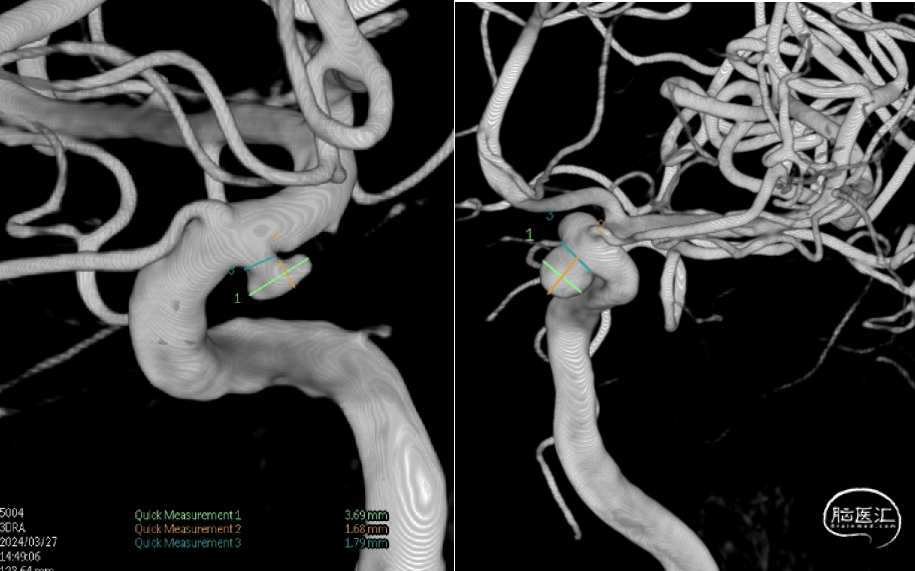

术前检查

DSA:双侧眼段动脉瘤

1.左侧颈内动脉C5段动脉瘤

2.右侧颈内动脉C5段动脉瘤术后